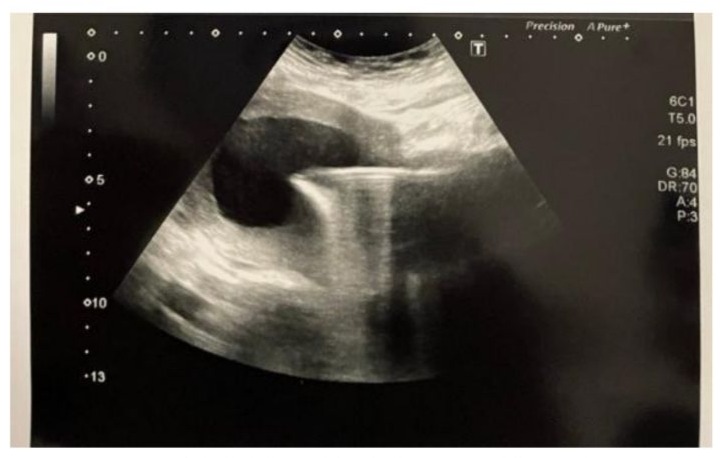

- Drainage of hematometra under general anaesthesia was performed through cervical dilatation under ultrasound guidance, due to worsening pelvic pressure symptoms and progressive distension seen on imaging. See pic [1,2]

Figure 1: Abdominal Ultrasound Showing Hematometra, Before Operation.